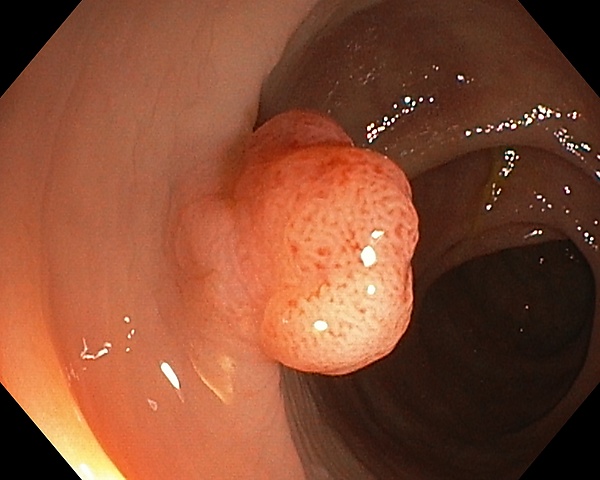

Колоноскопи́я, также фиброколоноскопия или ФКС — медицинский эндоскопический диагностический метод, во время которого врач осматривает и оценивает состояние внутренней поверхности толстой кишки при помощи эндоскопа. Колоноскопия даёт возможность визуально диагностировать такие заболевания, как образование язвы, полипы и др., а также провести биопсию и удалить эти поражения. Колоноскопия позволяет удалять полипы размером от долей миллиметра до 30-40 мм (в зависимости от их строения решение об удалении принимается во время первичного осмотра). Сразу после удаления полипа его можно исследовать в гистологической лаборатории и определить тип его строения. Это поможет спрогнозировать риски развития онкологических заболеваний у пациента в дальнейшем.

Удаление полипов при колоноскопии - важная процедура, позволяющая исключить вероятность развития злокачественного перерождения полипа.